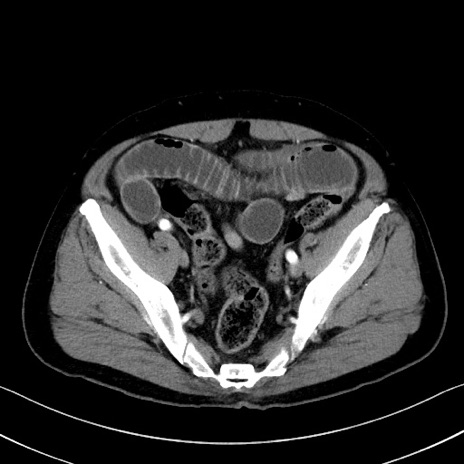

症例35(横断像)

【症例】70歳代 男性

【主訴】腹部膨満、嘔吐

【現病歴】昨日より腹部膨満感出現。本日増悪し、仙痛出現。嘔吐あり、受診。

【既往歴】糖尿病、胆摘後

【身体所見】BP 149/80mmHg、HR 74/min、BT 35.9℃、腹部:膨満、軟、圧痛なし。腸雑音減弱あり。上腹部正中切開瘢痕あり。

【データ】WBC 13500、CRP 1.72